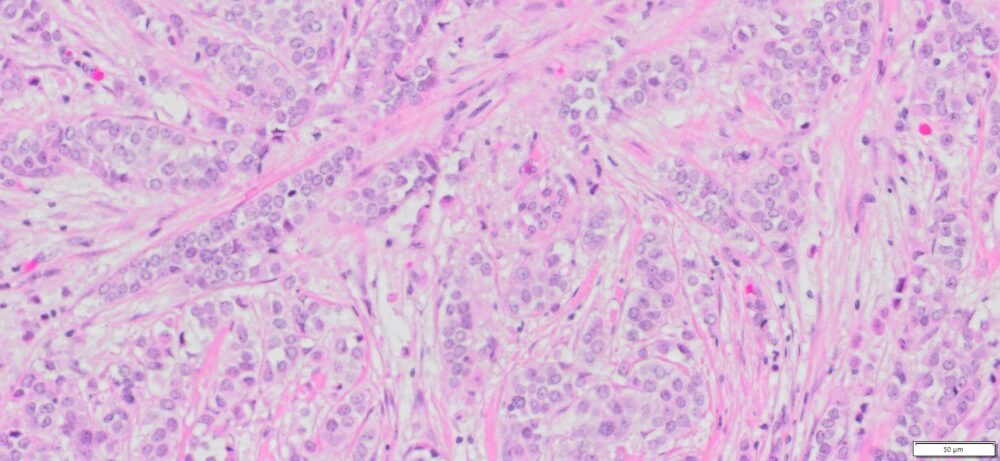

Description

| SKU# | Organ | Pathology Diagnosis | Therapies (Chemotherapies ,radiation and Hormone) before Collection of Sample |

Gender/Age (year) | Tumor Area(%) | Tumor Grade | TMN/Stage | ER,PR & HER2 IHC Data |

| HuPS-02032T1 | Breast | Invasive lobular carcinoma | No | Female/47 | 45 | II | pT1c pN0Mx | ER(+)/PR(+)/Her2 (+),E-Cadherin (-) |